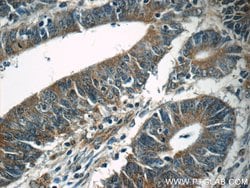

| Immunohistochemistry (Paraffin), Western Blot | |